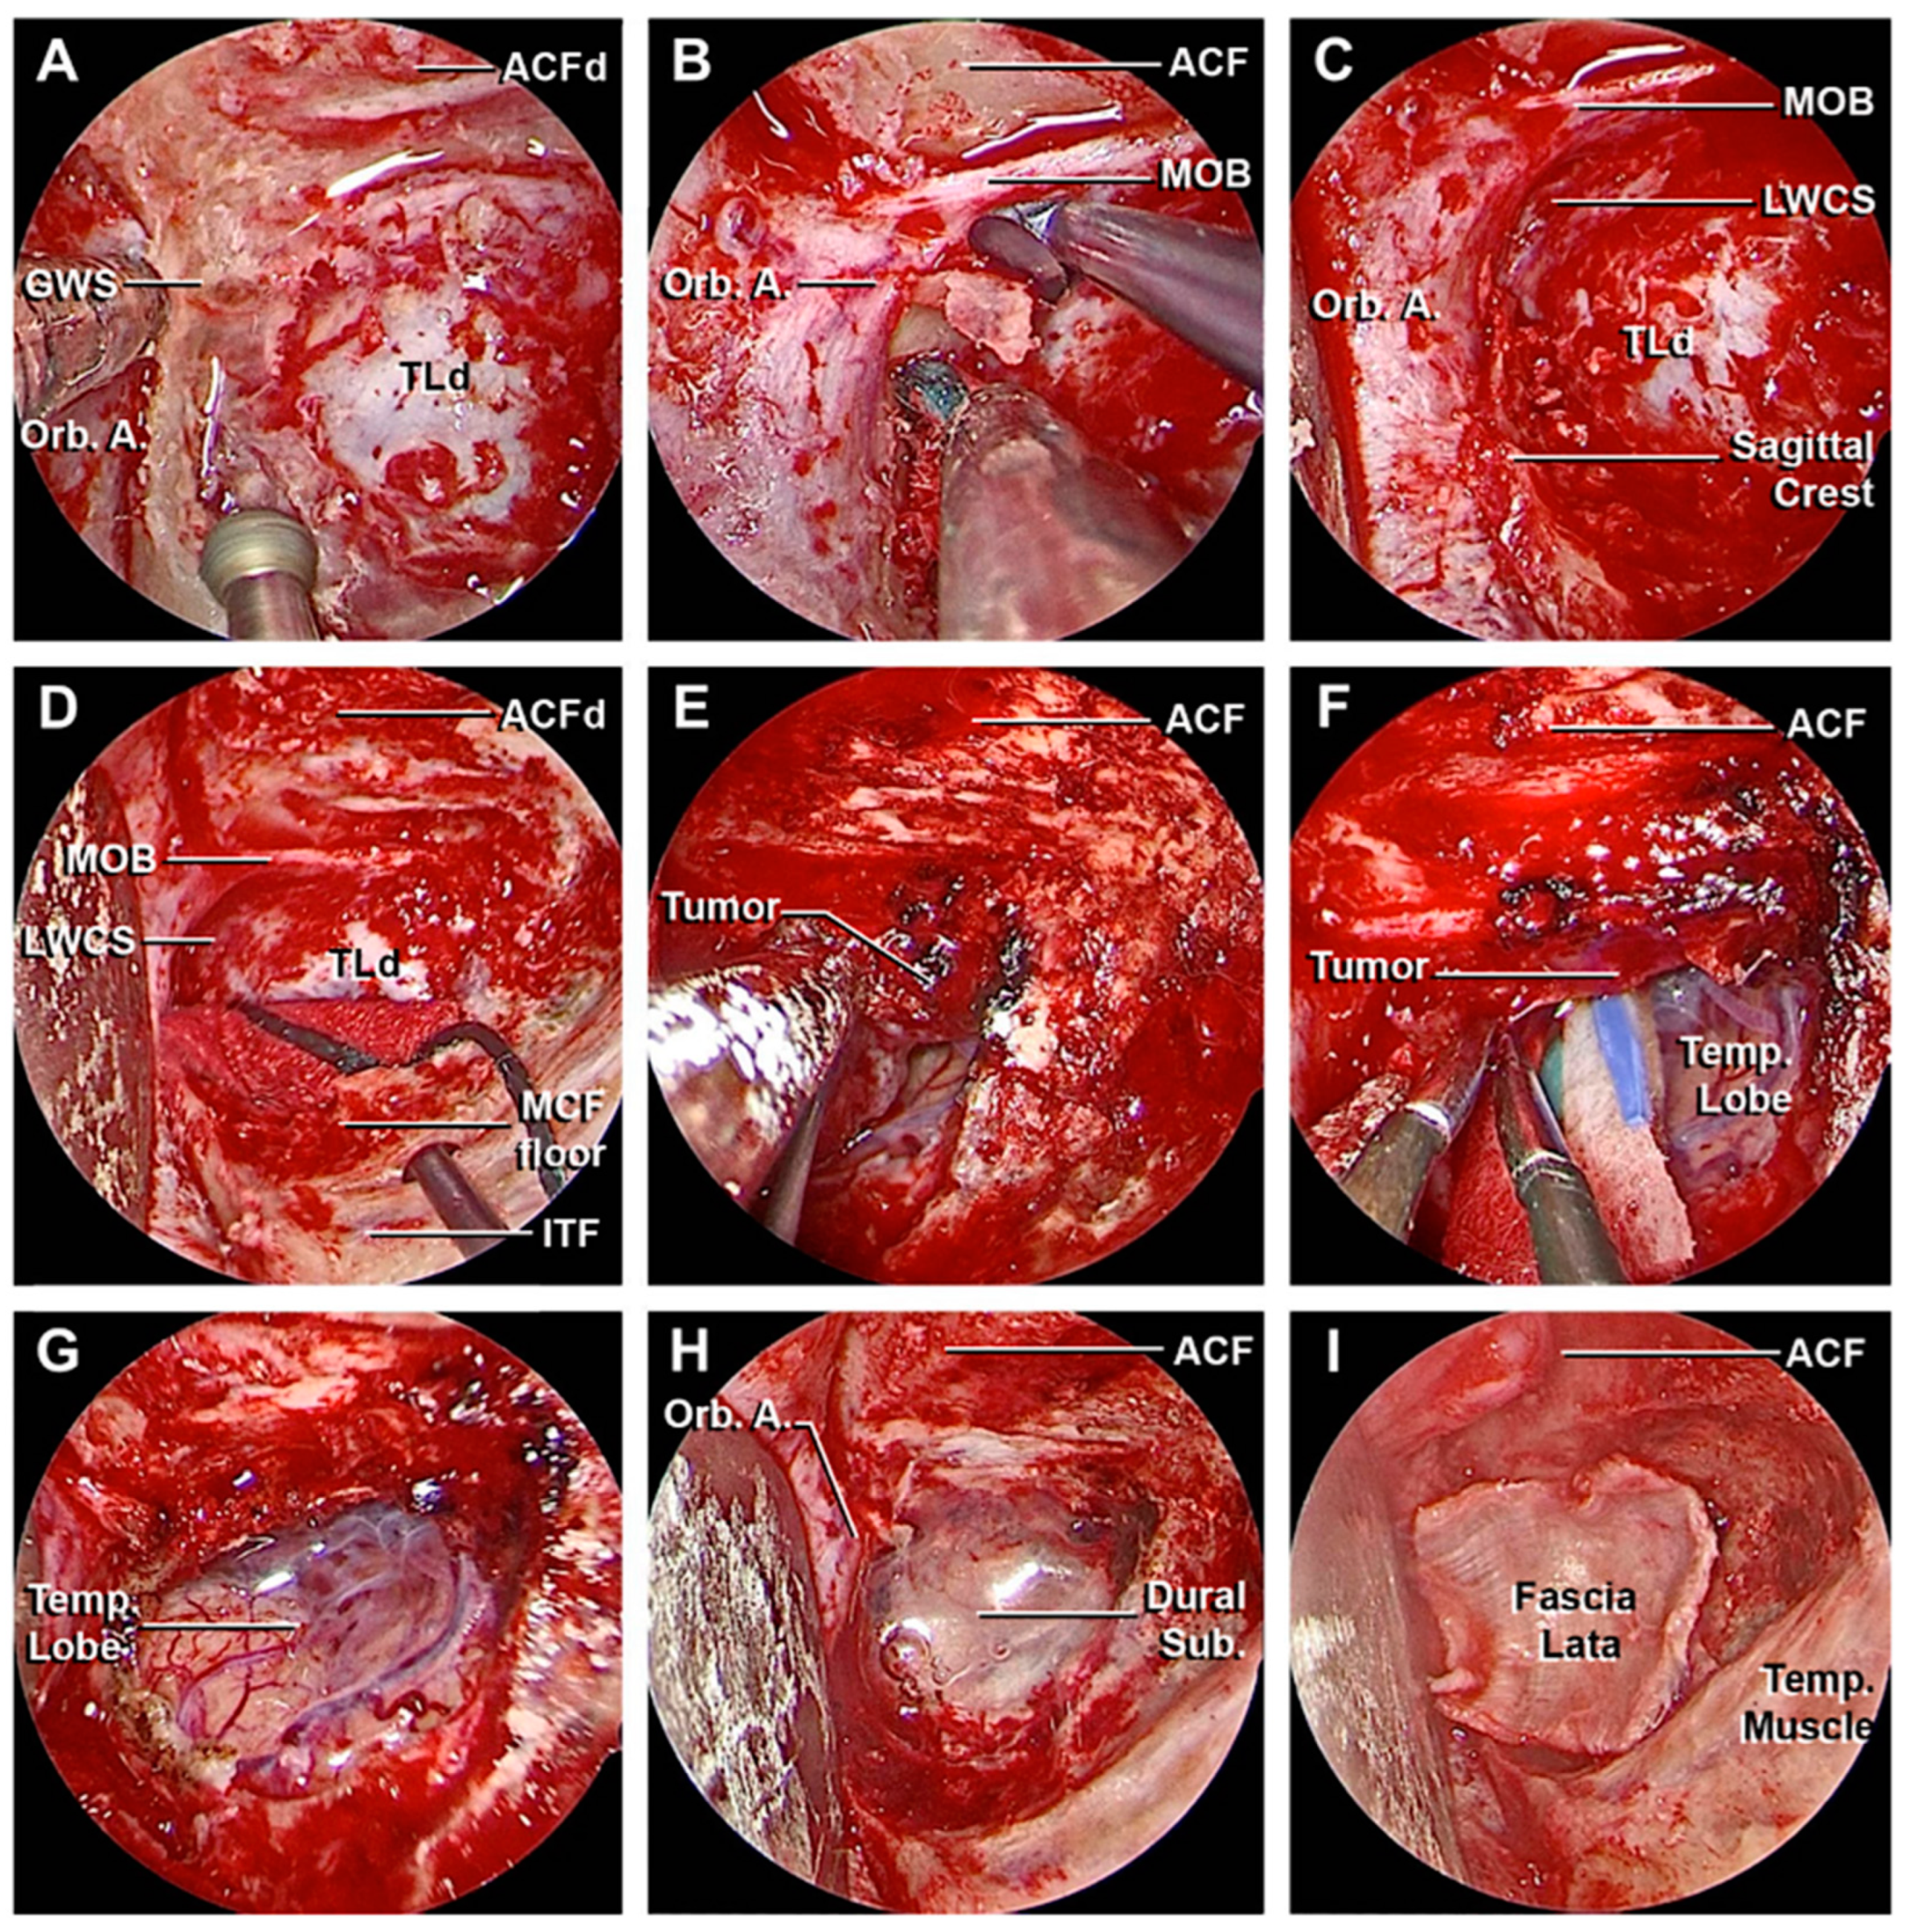

3.1. Step-by-Step Dissection

3.1.1. Craniectomy

3.1.2. Access to the Middle Fossa and Petrous Apex

3.1.3. Access to the Lateral Wall of the Cavernous Sinus and Anterior Clinoidectomy

3.3. Clinical Cases

3.3.1. Case 1

3.3.2. Case 2

3.3.3. Case 3